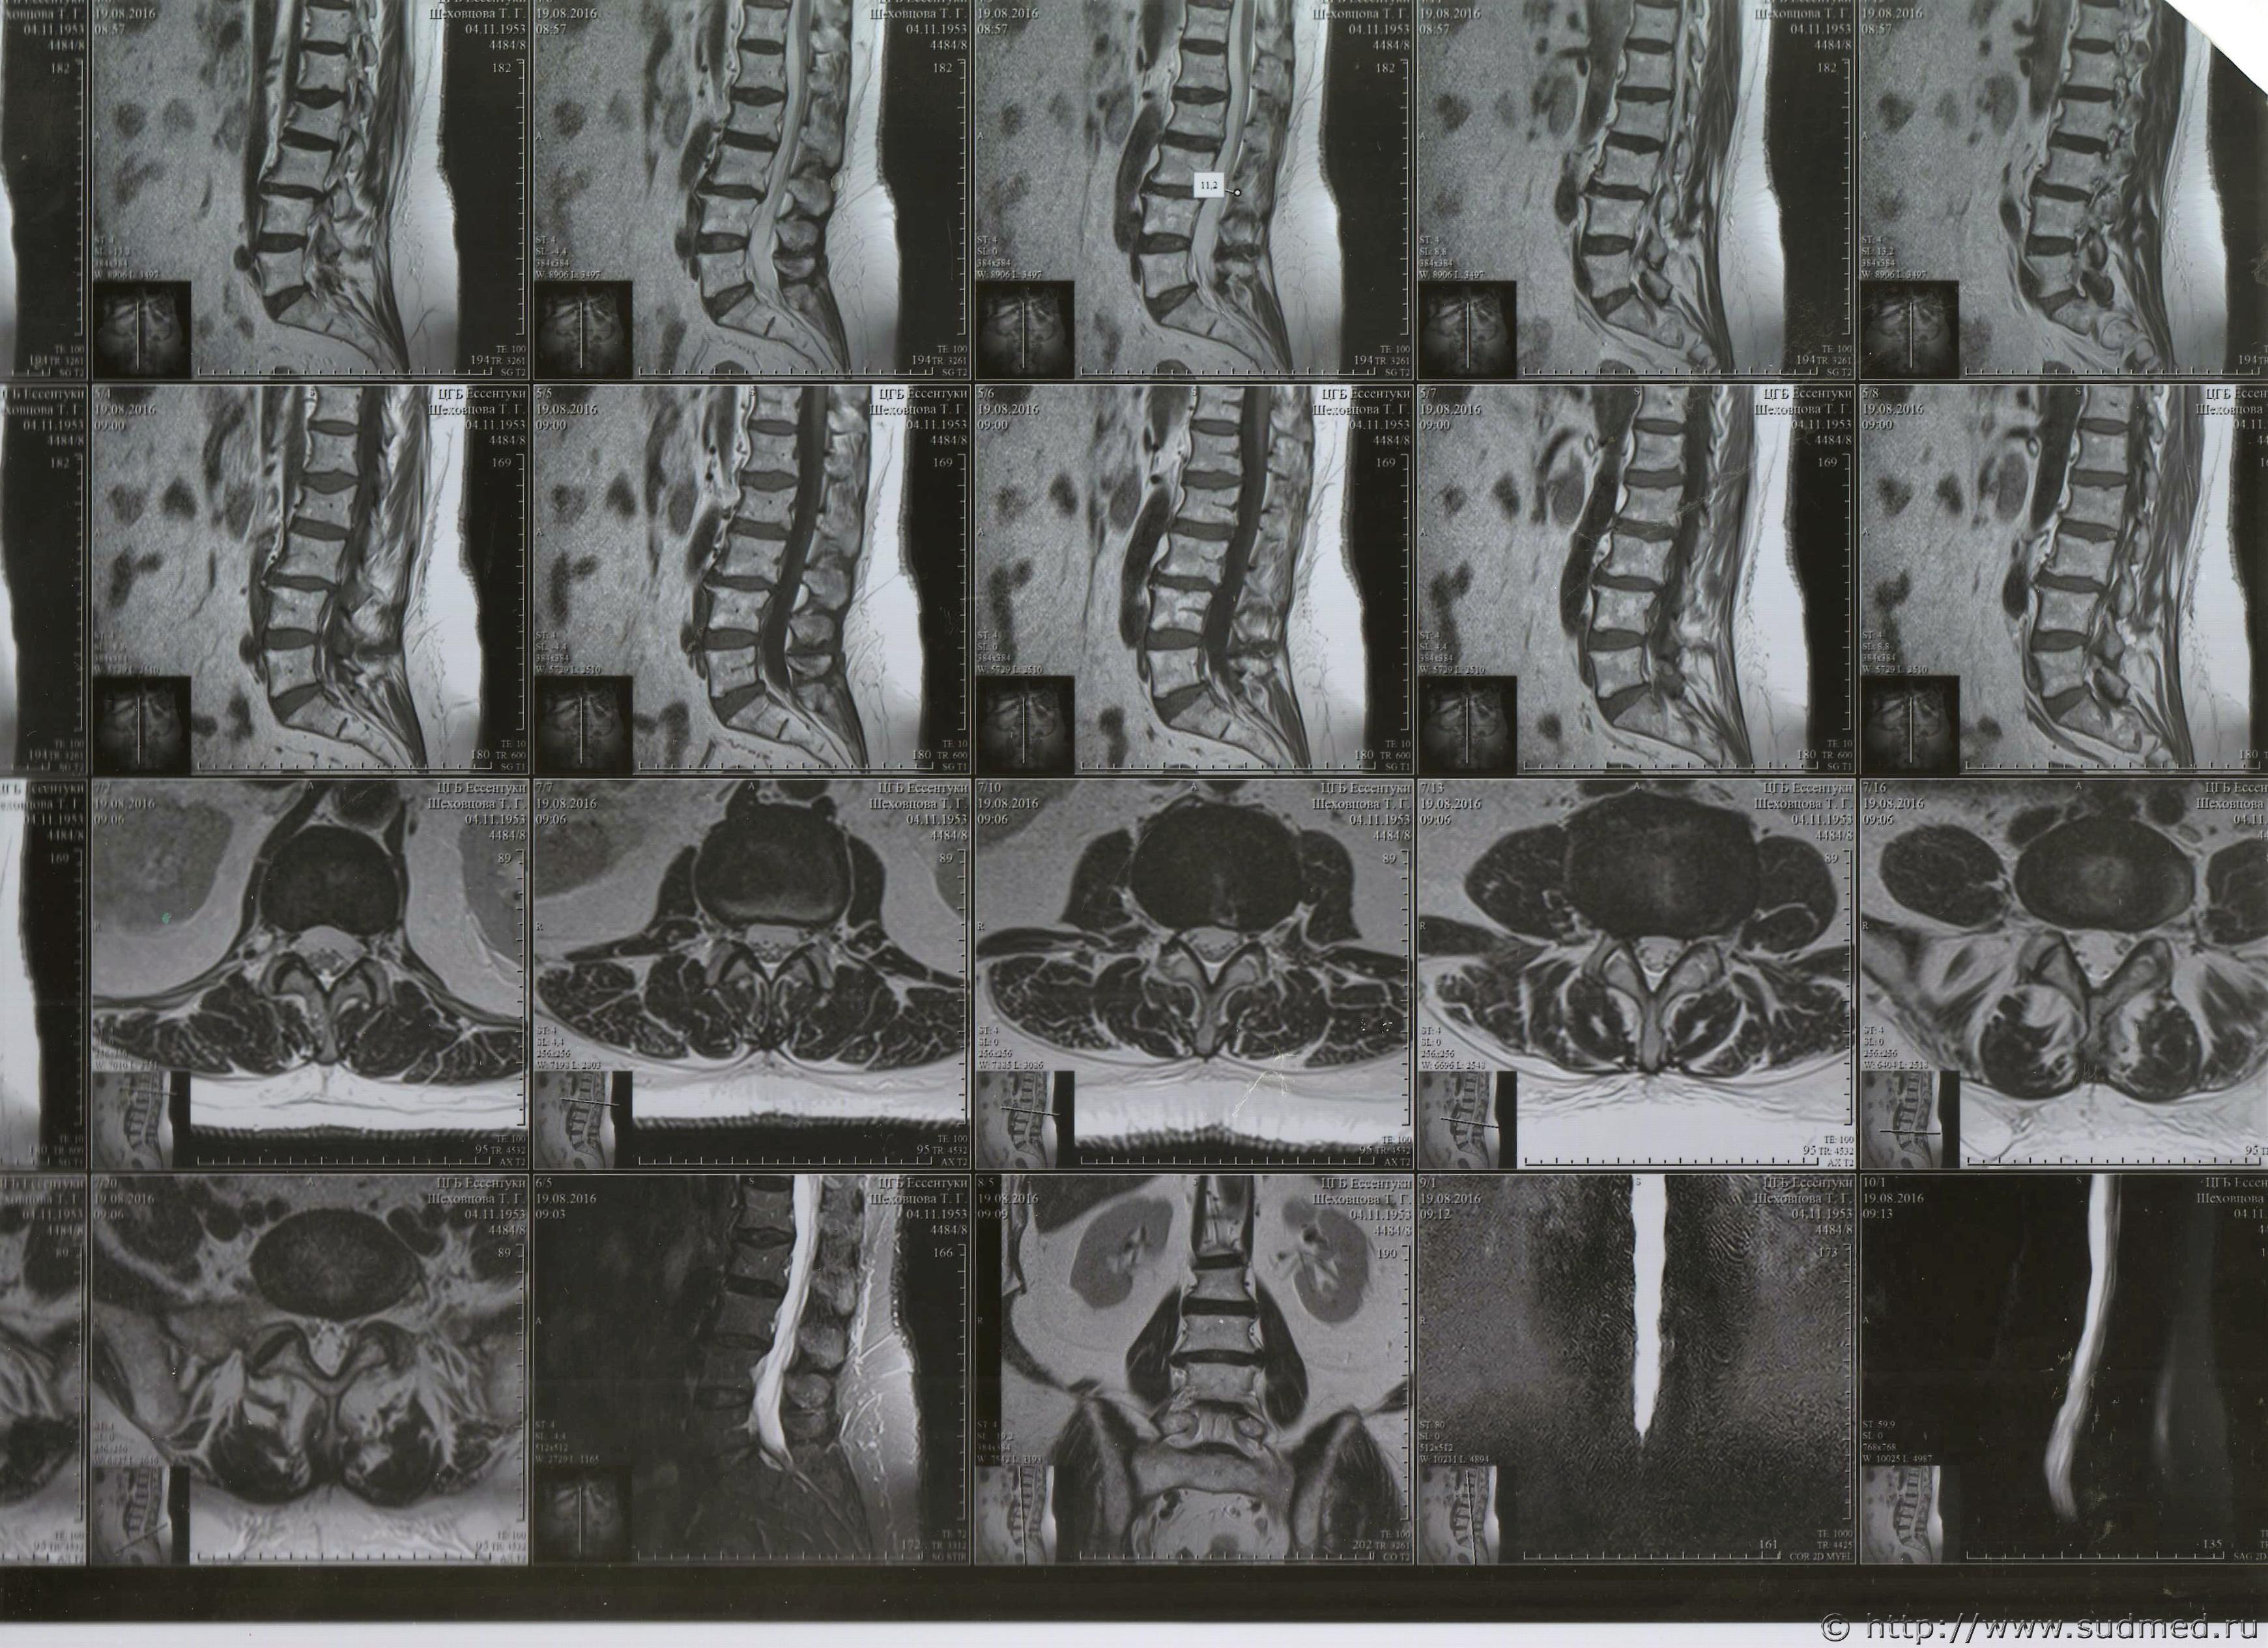

1. сделано 20.09.2015 г. заключение:

МРТ картина компрессионного перелома тела L2 позвонка.

Дегенеративно-дистрофические изменения поясничного-крестцового отдела позвоночника.Нарушения статики пояснично-крестцового отдела позвоночника. Грыжи дисков L1-S1/ Спондилоартроз. Относительный стеноз позвоночного канала.

Сигнал от костного мозга позвонков диффузно неоднородный- для детализации костных патологических изменений рекомендуется компьютерная томография.

2. Заключение КТ от 05.10.2015 г.

КТ-признаки консолидированного компрессионного перелома тела L2. Постравматического спондилоартроза, спондилеза, постравматического остеохондроза поясничного отдела позвоночника, Циркулярные, дорзальные протрузии МПД L2-L5-S1/

Дорзальная грыжа МПД L5-S-1

3/ Заключение: МРТ от 16.02.2016 г.

Консолидированный компрессионный перелом тела L2 с передней клиновидной компрессией 3 степени. МР картина остеохондроза ПОП, " ст.- в ПДСL2-L3, L4-L5, L5-S1 задние протрузии дисков сагиттальный размер которых до - 3 мм, протрузии компремируют дуральный мешок.

Уважаемые доктора, нужны ли снимки по перелому правой голени? и Заключения по МРТ и КТ.Ранее представляла результаты обследования...Сделала копию снимков по КТ и МРТ( только вот какого качества получились не знаю.)

Посмотрите, пожалуйста